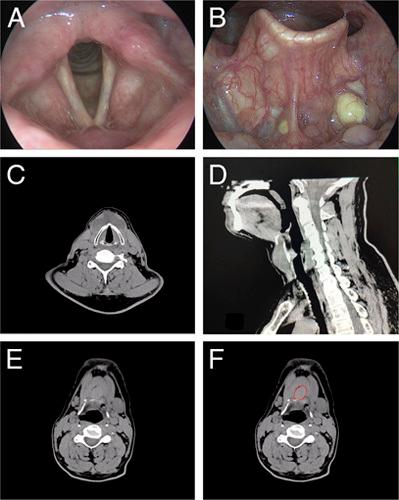

As one of the most common congenital neck masses, thyroglossal duct cyst (TGDC) developed from the residual ductal epithelial cells in any remnants of thyroglossal duct. However, the reports of double TGDCs were rare. A 60-year-old male was referred to our department because of the presentation of an anterior neck mass. Only a hypodense oval mass inferior to hyoid bone was shown by computed tomography. During the Sistrunk operation, the dumbbell-shaped double TGDCs with the hyoid bone as the pivot were excised. No recurrence was observed. Before surgery, ultrasonography and computed tomography or magnetic resonance imaging should be conducted to verify the locations and sizes of TGDCs. During Sistrunk procedure, the rims of hyoid bone should be checked to avoid possible duct remnants.

作为最常见的先天性颈部肿块之一,甲状舌管囊肿(TGDC)是由甲状舌管任何残留的导管上皮细胞发育而来。然而,双 TGDC 的报道很少见。一名 60 岁男性因出现颈部前肿块而被转至我科。计算机断层扫描仅显示位于舌骨下方的低密度椭圆形肿块。在施行 Sistrunk 手术时,我们切除了以舌骨为枢轴的哑铃状双 TGDC。未观察到复发。手术前,应进行超声检查、计算机断层扫描或磁共振成像以验证 TGDC 的位置和大小。在行 Sistrunk 手术时,应检查舌骨边缘以避免可能的导管残留。